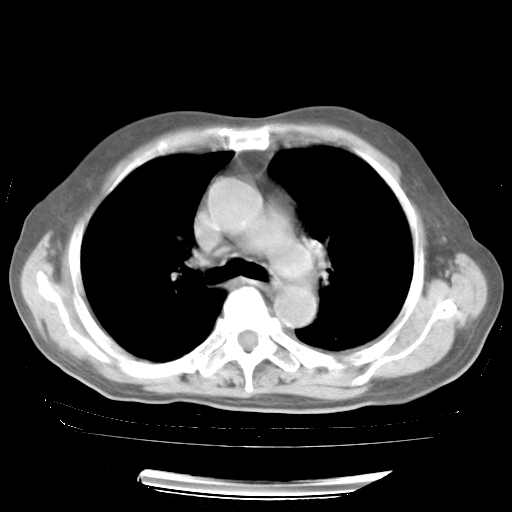

4月28日肺部CT——再次出现类似去年5月9日——透光度降低,“间质性”改变。